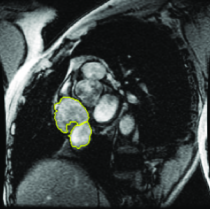

Appearance is one of the most important visual cues to distinguish between different structures in an image. Appearance is described by studying the distribution of different features such as intensity values in gray-scale images, color, and texture inside each object. In most cases, appearance models are incorporated into the data term in (2) and (7). The purpose of incorporating appearance prior is to fit the appearance distribution of the segmented objects to the distribution of objects of interest, e.g. using Gaussian mixture model (GMM) (Rother et al., 2004). In the literature, there are two ways to model the appearance: 1) adaptively learning the appearance during the segmentation procedure, and 2) knowing the appearance model prior to performing segmentation (e.g. by observing the appearance distribution of the training data). In the former case, the appearance model is learned as the segmentation is performed (Vese and Chan, 2002) (computed online). In the second case, it is assumed that the probability of each pixel belonging to particular label is known, i.e. if represents a particular set of feature values (e.g. intensity/color) associated with each image location for object, then it is assumed that is known (or pre-computed offline). This probability is usually learned and estimated from the distribution of features inside small samples of each object. Figure 9 illustrates the probability of different structures (the kidney, the tumour, and the background) in an endoscopic scene. A lower intensity in Figures 9(b-d) corresponds to higher probability.